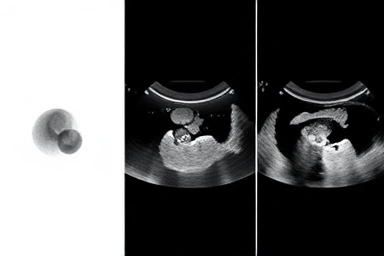

임신 중 초음파는 아기 건강 확인의 핵심이며, 종류별 시기와 비용 이해가 중요합니다.

- 초기엔 일반 초음파, 20~24주엔 정밀 초음파로 태아 발달을 꼼꼼히 봅니다.

- 입체 초음파는 24~29주에 태아 외형을 3D로 확인하며, 시기 따라 모습이 달라집니다.

초음파 검사는 태아 건강 확인의 핵심입니다. 시기별 검사로 잠재적 문제를 조기에 발견합니다.

임신 6~10주 일반 초음파는 임신 확인과 초기 발달을 봅니다. 심장 소리, 크기, 주수 파악이 중요합니다.

20~24주 정밀 초음파는 태아 장기, 골격 이상을 정밀 진단합니다. 20~40분 소요될 수 있습니다.

입체 초음파(3D/4D)는 태아 외형을 생생하게 보여주며, 24~29주(26~28주 권장)에 가장 이상적입니다.

24~29주, 특히 26~28주에 태아 모습이 가장 선명합니다. 아기 협조가 중요합니다.